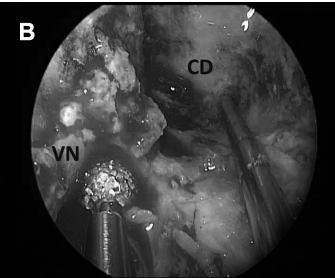

▼进行了对侧单侧入路和宽蝶窦切开术(图8A)。

▼对斜坡骨下方和横向钻孔磨骨,扩大手术通道,并识别定位及保护右侧翼管神经(图8B,钻头上方)。

▼在颈内动脉(ICA)后方轻柔钻孔,避免损伤颈内动脉导致出血(图8C)

CD,斜坡凹陷;S,蝶鞍;SR,蝶嘴;T,肿瘤。